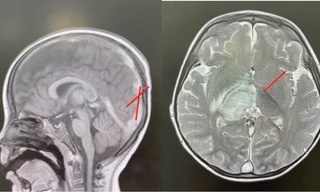

TPO - Bé trai 2,5 tuổi được Bệnh viện Nhi Đồng 1 cứu sống sau khi bị đột quỵ do một tình trạng y khoa hiếm gặp – huyết khối tĩnh mạch nội sọ liên quan đến bệnh lý di truyền homocystin niệu.